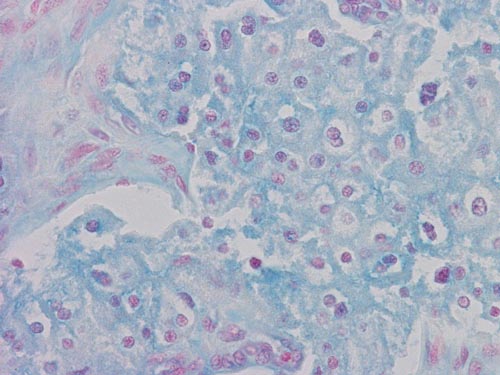

Hale's colloidal Iron

Colloidal iron: The cytoplasm of this tumor is stained blue with Hale's colloid iron stain.

• Although many of the cells have rather eosinophilic cytoplasm, distinct perinuclear halos are present in most of the tumor cells. This case can be considered an eosinophilic variant but the classic features of a chromophobe renal cell carcinoma are still rather distinct. In some cases with more extensive eosinophilic changes than the current one, those tumors may mimic oncocytoma. A special stain for colloidal iron or electron microscopy would be very helpful for diagnosis. Ultrastructurally, oncocytoma will contain numerous mitochondria and chromophobe carcinoma will contain numerous small cytoplasmic vesicles. It would, therefore, be a valuable practice toe procure a sample for electron microscopy particularly when the gross pathology deviates from renal cell carcinoma which typically have golden yellow cut surface.